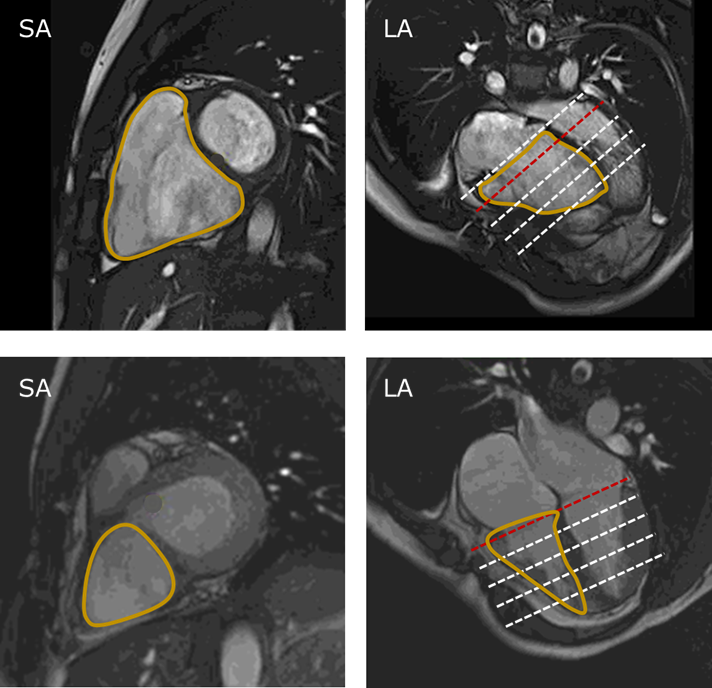

Amazon.co.jp: Learning Cardiac CT: A Board Review : Sharim,

Amazon.co.jp: Learning Cardiac CT: A Board Review : Sharim, Amazon.com: Learning Cardiac CT: A Board Review,

Amazon.com: Learning Cardiac CT: A Board Review, Right Atrial Compression From Biodebris Associated With Long,

Right Atrial Compression From Biodebris Associated With Long, M&Ms-2 Challenge,

M&Ms-2 Challenge, CBAR-UNet: A novel methodology for segmentation of cardiac

CBAR-UNet: A novel methodology for segmentation of cardiac[amosjoption] ロングパンツ レディース スポーツ ワイドパンツ ズボン ハイウエスト 大きいサイズ ゆったり 美脚 カジュアル ゆったり フィットネス ランニング ダンス お出掛け 通勤 普段履き 旅行 クリスマス ハロウィン